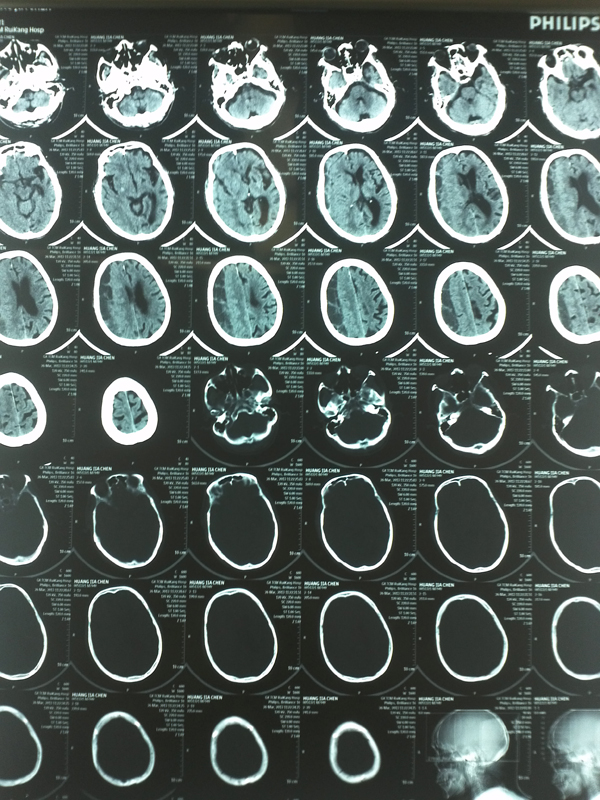

原来,10多天前黄爷爷不慎摔倒,之后逐渐出现手脚无力,言语不清,茶饭不思,甚至胡言乱语。他的子孙们急忙将其送到我院就诊,紧急行头颅CT检查发现黄爷爷颅内有瘀血,瘀血量达100多毫升,一般颅内瘀血超过30ml就有生命危险了,黄爷爷如此大量的颅内瘀血压迫脑组织,不马上手术将有生命危险。

黄爷爷被马上送入了神经外科重症监护室,神经外科专家们紧急讨论老人的治疗方案。分析老人的头颅CT后,提示老人是硬膜下血肿,血肿呈分隔状态,分成几个部分,单纯引流手术是无效的。开颅手术可以较彻底的清除血肿,解除脑的压迫,但是黄爷爷已经年近百岁,身体极其虚弱,这样的身体状况怎么能耐受开颅手术?经过专家们反复讨论,最后决定采用目前先进的神经内镜微创手术为老人清除血肿。经过充分术前准备后,黄爷爷被送进了手术室,经过麻醉后,神经外科专家张鉴文副教授在老人头上做一个拇指大骨孔,然后将神经内镜伸进颅内,见到老人硬膜下血肿比CT所见更加严重,血肿机化、包膜厚、分隔成很多个小房,与脑组织粘连严重。张鉴文副教授在神经内镜辅助下仔细地将血肿及其包膜全部清除,经过1个多小时手术,为老人解除了险境。术后老人恢复良好,现在已经能下床行走。

以下为其头颅CT所见,右侧慢性硬膜下血肿呈分隔,包膜较厚。脑受压严重。